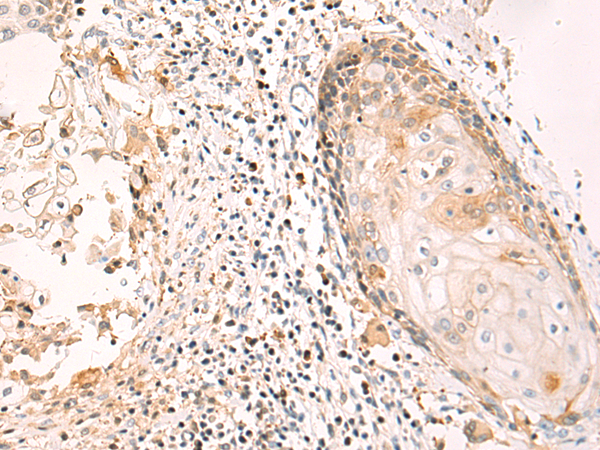

IHC positive control: |

Human esophagus cancer and Human tonsil |

IHC Recommend dilution: |

50-100 |